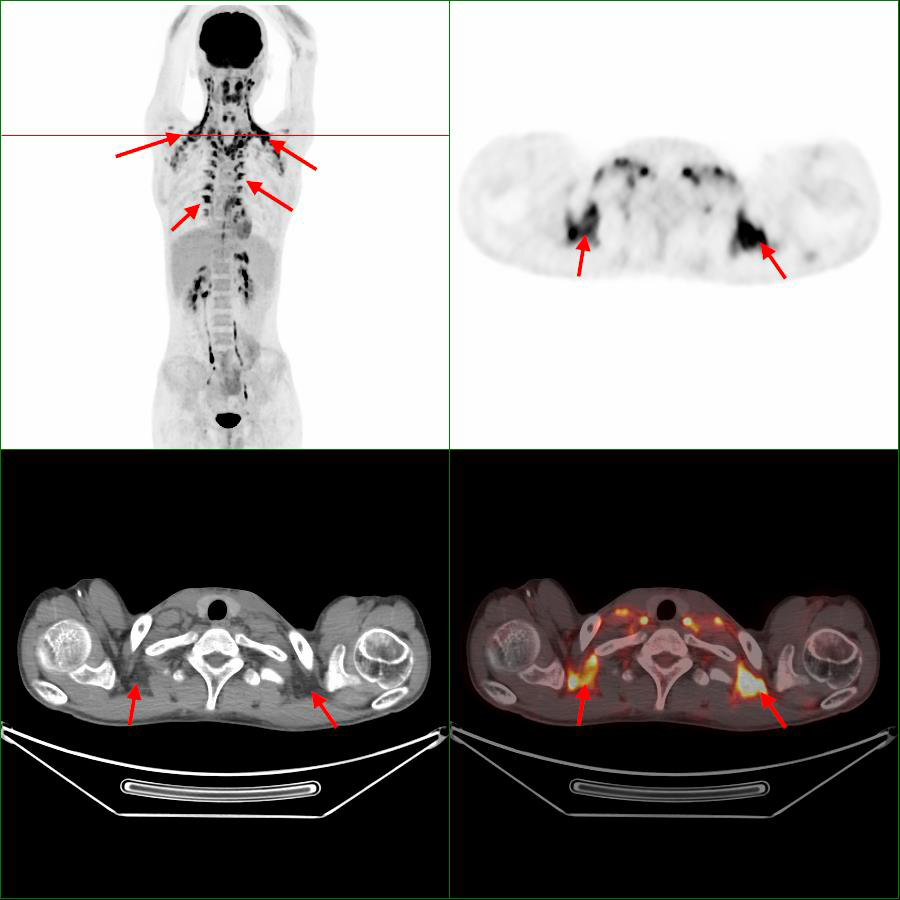

在寒冷環(huán)境下,人體為了維持體溫,棕色脂肪會迅速地分解和消耗,以釋放出能量來維持體溫,形成高代謝攝?。▓D1,箭頭),被PET/CT檢測到其顯影。對讀片醫(yī)生來說,它是偽影,會掩蓋該區(qū)域的病灶檢出,影響對病灶的判斷。當對診斷有嚴重影響時,不得不改期再次進行PET/CT檢查,造成不必要的時間和經(jīng)濟損失。

圖1 第1次顯像,箭頭指示為棕色脂肪顯影